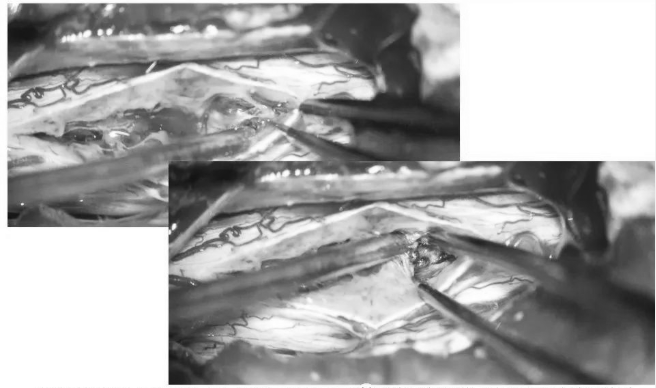

▼逐步显露血管瘤腹侧面

▼血管瘤完整取出

▼测量瘤腔大小,明确肿瘤全切